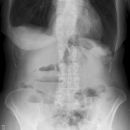

Abdomen

Aerobilie